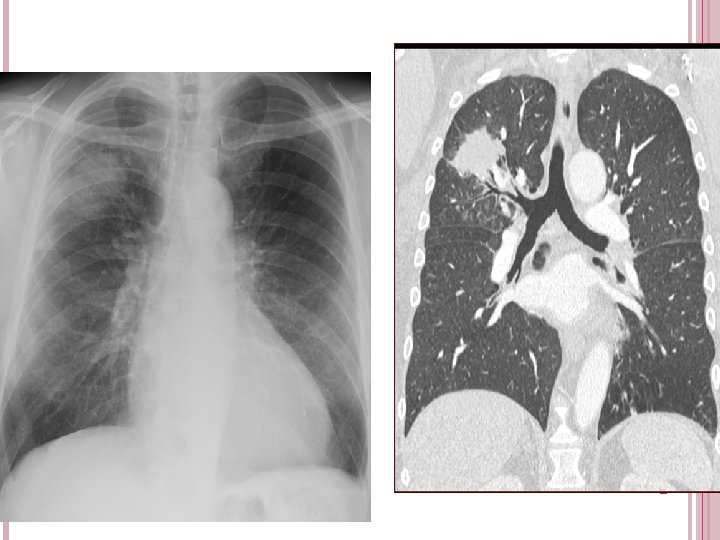

Tuberculose La présentation radioclinique dépend du degré d'immunodépression. Au stade précoce, la présentation radioclinique est identique à celle des patients immunocompétents. À un stade plus avancé, on retrouve quelques caractères particuliers : infiltration des lobes inférieurs, diffusion parenchymateuse à type de miliaire, adénopathies médiastinales, dissémination extrapulmonaire. le taux de CD 4 est inférieur à 100/mm 3, la radiographie peut être normale avec cependant une pullulation de bacilles acidoalcoolorésistants (BAAR) Le diagnostic de certitude repose sur la mise en évidence de BAAR à l'examen direct de différents prélèvements - expectoration, LBA, liquide pleural, prélèvement d'organe extrathoracique atteint - avec culture positive à M. tuberculosis. La présence de granulome tuberculoïde sur un prélèvement histologique (exemple : biopsie transbronchique) Trt : 2 RHZE/4 RH